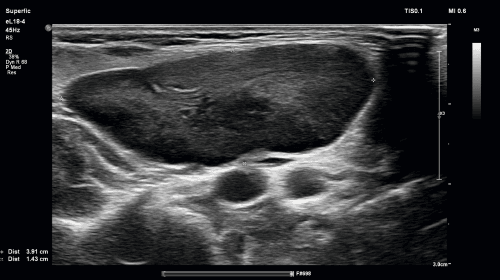

Niemowlę trzymiesięczne zostało przyjęte do Kliniki z powodu obrzęku w szyi po stronie prawej. Przy przyjęciu dziecko było w dobrym stanie ogólnym; w badaniu fizykalnym zwracała uwagę nieco zaczerwieniona skóra w okolicy prawego kąta żuchwy oraz wyczuwalne powiększone węzły chłonne szyi podżuchwowe z przewagą po stronie prawej. W badaniach laboratoryjnych nie stwierdzono nieprawidłowości. W USG poniżej małżowiny ucha prawego stwierdzono zmieniony zapalnie węzeł chłonny 16 x 14 x 12 mm, o nierównych obrysach z obrzękiem sąsiednich tkanek, w jego części obwodowej uwidoczniono obszar płynowy bez przepływu dopplerowskiego. Dziecko przeniesiono do Kliniki Chirurgii Dzieci, gdzie wykonano drenaż. W badaniu mikrobiologicznym ropnej treści wyhodowano gronkowca złocistego. Ropień w obrazowaniu USG to guz hipoechogeniczny bez pasmowatego echa wnęki, odgraniczony torebką o nieregularnej grubości, z wewnętrznymi odbiciami lub przegrodami spowodowanymi obecnością treści ropnej i rozkładających się tkanek (tzw. debris). Widoczne mogą być echogeniczne ogniska z cieniami akustycznymi o charakterze artefaktów, które odpowiadają występowaniu powietrza. Obrazowanie dopplerowskie wykazuje brak przepływu. Gdy dojdzie do przerwania ciągłości torebki ropnia (tzw. ropowica), granice między sąsiadującymi strukturami stają się nieostre. W przebiegu ostrego zapalenia węzłów chłonnych, zanim dojdzie do wytworzenia się klasycznego obrazu ropnia, często mamy do czynienia z drobniejszymi ogniskami martwicy wewnątrz węzła chłonnego oraz z podwyższoną echogennością sąsiednich tkanek. W badaniu dopplerowskim stwierdzimy wówczas amputację przepływu w miejscach nekrozy. Zdarza się, że już na takim etapie węzły chłonne wymagają interwencji chirurgicznej. Wspomnieć należy, że w przypadku, gdy podejrzewamy formowanie się ropnia w obrębie grup węzłów chłonnych szyi niedostępnych badaniem USG (przede wszystkim węzły zagardłowe), należy wspomóc się obrazowaniem za pomocą KT lub MRI.